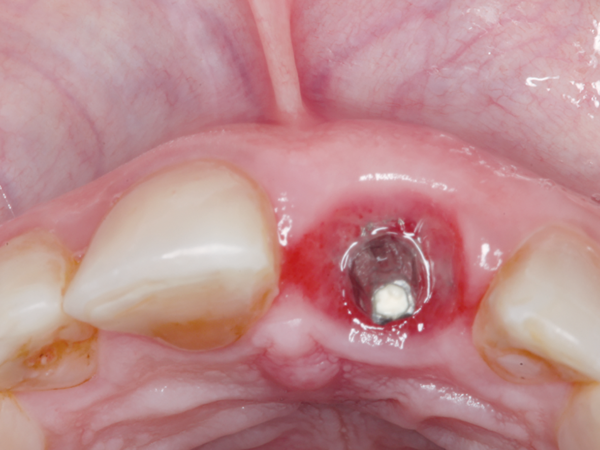

Outros fatores de risco, como fumo, altura do pilar protético em relação à crista óssea e diâmetro do implante, também foram avaliados. Dentre estes, pilares com cinta de 0,8 mm (Figura 3) foram mais suscetíveis à perda óssea quando comparados aos pilares de cinta maior do que 1,5 mm (Figura 4).

Figura 3 – Peri-implantite em implante cone-morse com pilar de cinta 0,8 mm.